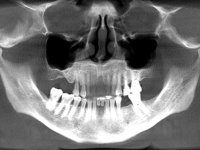

Female patient, 56 years-old, smoker. Teeth 41 and 31 with mobility grade III. Teeth 42 and 32 vital, with no mobility. After clinical and radiographic examination the extraction of central incisors was indicated.

• After two months, a CBCT scan to plan one dental implant and the type of bone regeneration to be performed. Due to the lack of mesiodistal space, the option for two dental implants was dropped.

After the CBCT evaluation, our option was to place the dental implant in the central position of the edentulous area for 4 mains reasons:

• Preservation of the bone in the mesial surfaces of the adjacent teeth.

• The thickness (buccal-lingual) was higher in the area.

• Biomechanical, the position was more favourable.

• The esthetic rehabilitation with gum-shade ceramics was easier with the implant placed in this position.